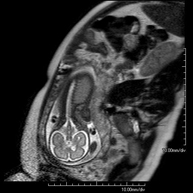

Foetal MRI

This non-invasive diagnostic procedure uses an electromagnetic field and radio waves (from a transmitter and receiver) to acquire high-definition anatomical images of the foetus in a pregnant woman. It is a radiation-free procedure. It can be performed from week 12 of pregnancy onwards and is safe for both the foetus and the mother. It is used when there is suspicion of some congenital morphological anomaly.